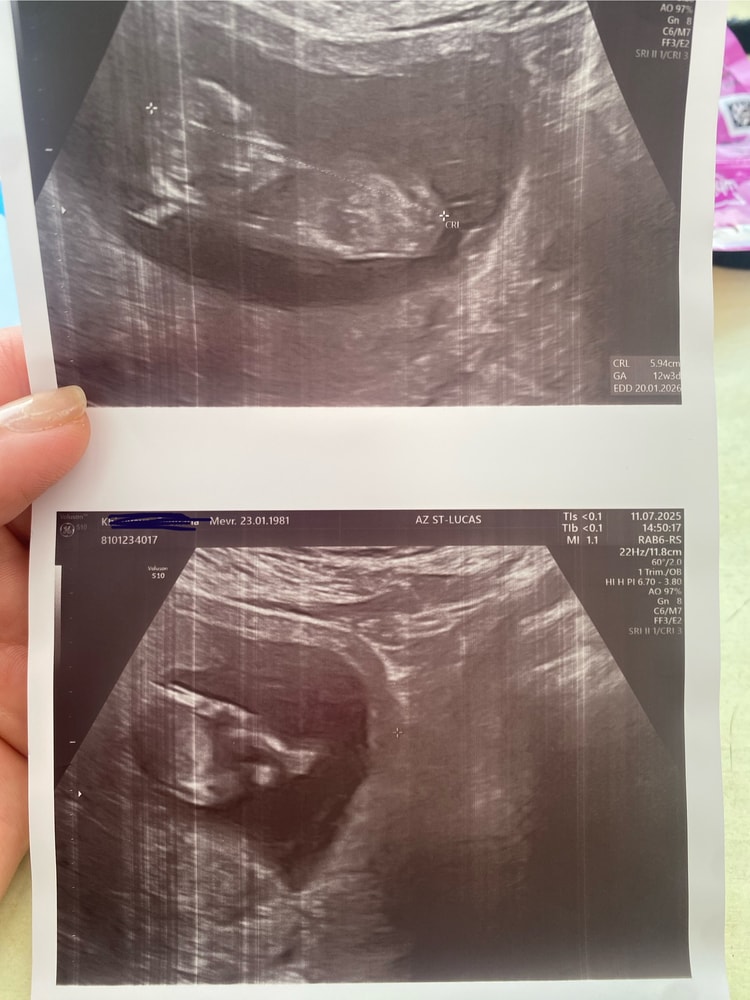

тут 12неделек⤵️

Ну что, так ждала этого момента, когда смело могу сделать тут запись, опубликовать пост,и вот сегодня 25/07 я с улыбкой на лице, со слезами радости, делюсь своей «ПОБЕДОЙ» Мой 11ый перенос, мой 12 по счету эмбриончик По Узи по анализам НИПТ -здоровый малыш,ну и у нас «🎀ДЕВОЧКА🎀 Мечта папина!!!Мамина душа!!! Папина радость!!! Господа Бога благодарю за все, за все испытания что он мне давал, за мое терпение,за все я благодарна в миллион раз 🥹😭🙏🙏🙏🙏 Разрыдалась сегодня прям в кабинете от счастья, с моей душевной и замечательным врачом/гинекологом мы по обнимались от радости☺️ потом посмотрели по УЗИ малышку, измерила - мы 9 см , пытались посмотреть личико но она так крутилась вертелась , головку туда сюда крутила, так смешно было, потом ручкой и ножкой стала играться, это было так милооо это было не вероятно, ребенок там уже кувыркался только так, мой доктор еще меня спросила « ты еще не чувствуешь шевелюшки» потому что она очень была подвижна+ расположение по задней стенке матки ☺️🎀 показала как бьется все четыре клапана♥️ показала все ручки ножки пальчики,сердечко слушали,все было очень радостно и я была ужасна спокойна ☺️🙏 Я только сейчас поняла , и почувствовала как можно дышать полной грудью🤭 без переживаний и волнений !!! мой беременный воздух стал сегодня другим миром !!!! Я просто нахожусь в эйфории !!!! Господи спасибо за все🙏